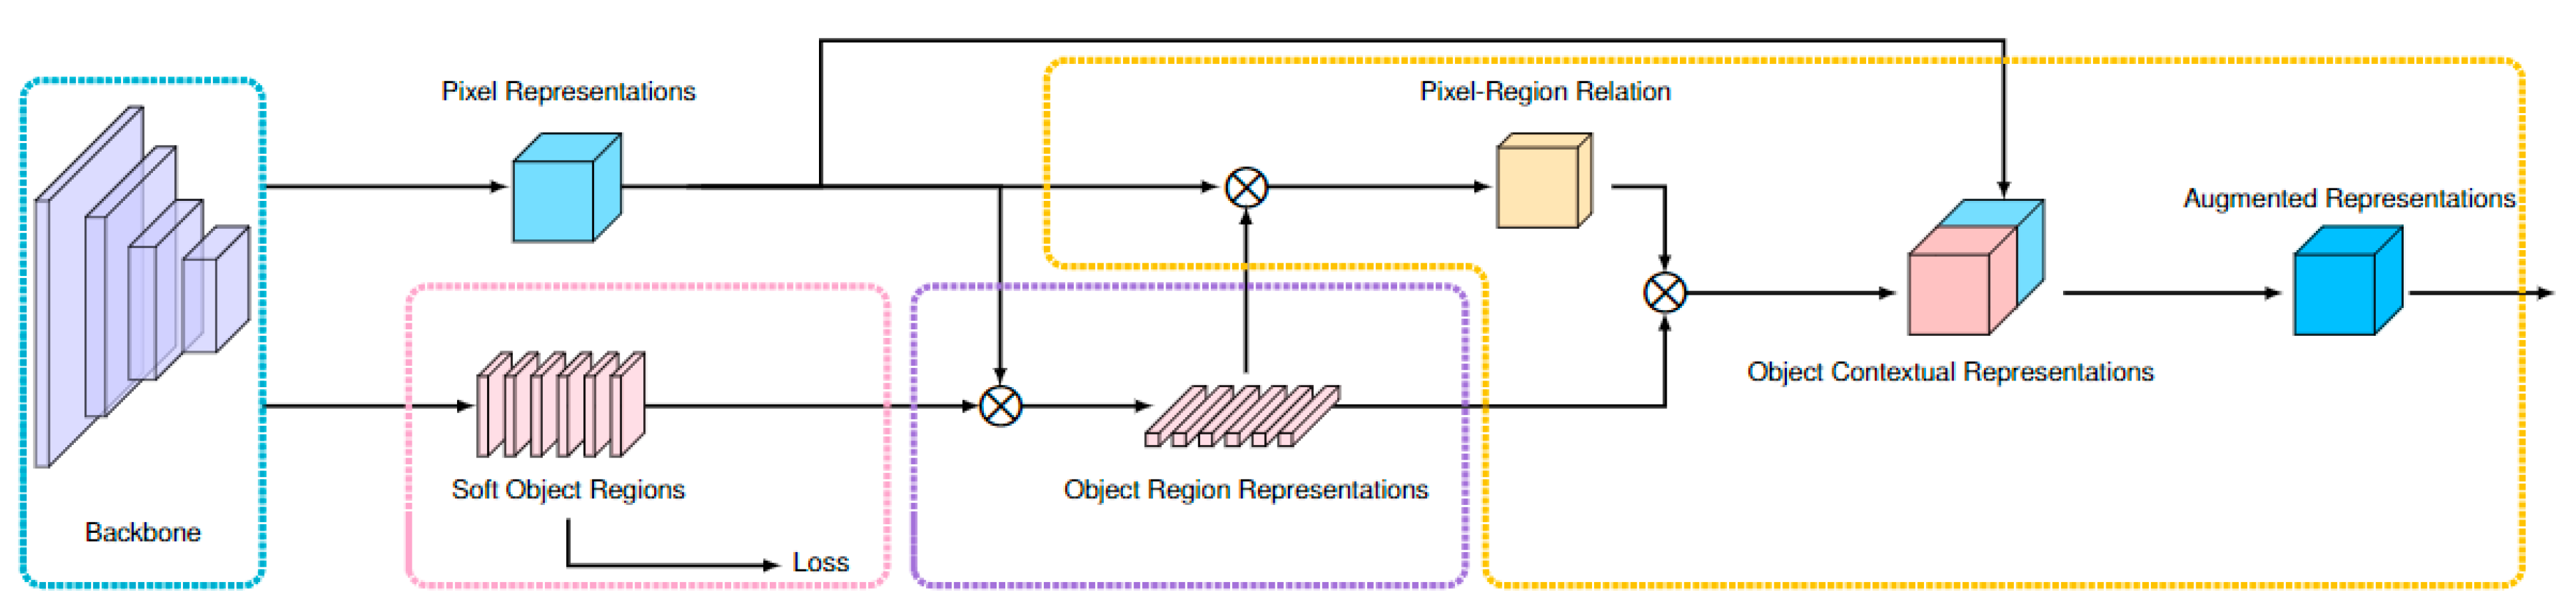

2.2. Development of the Algorithm